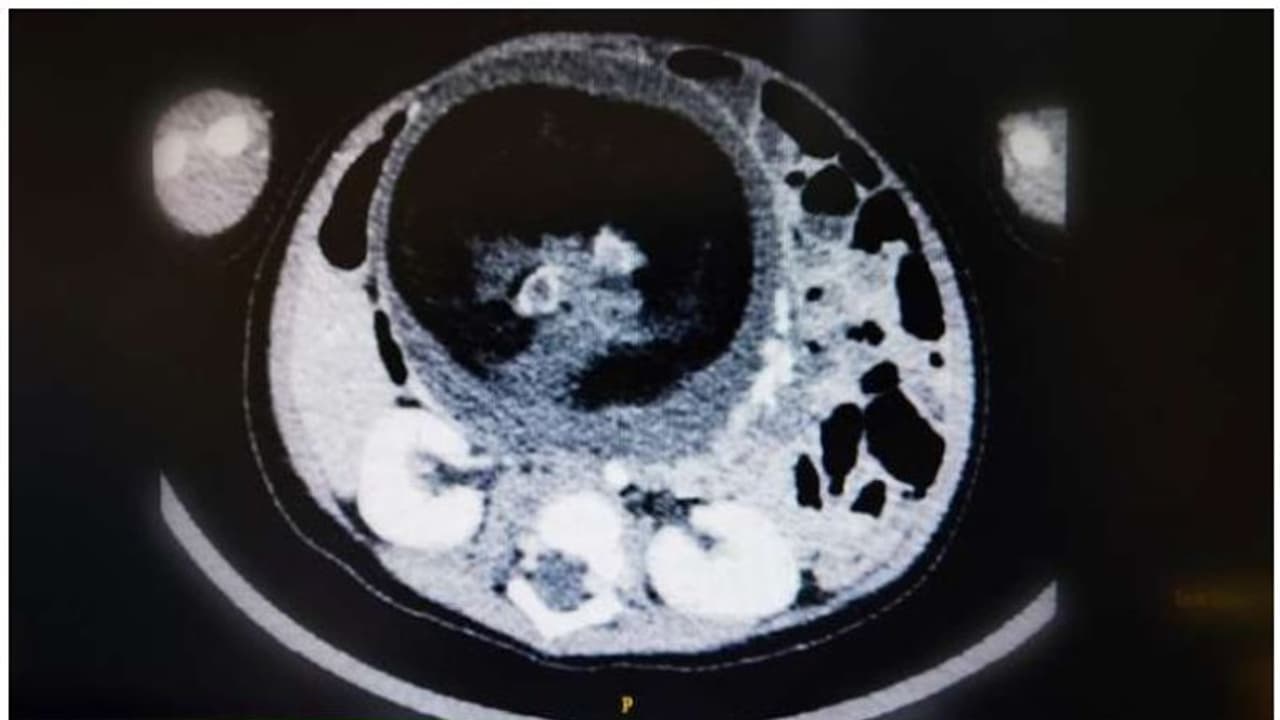

മസ്കറ്റ്: ഒമാനിലെ റോയല് ആശുപത്രിയില് എട്ടു മാസം പ്രായമുള്ള പെണ്കുഞ്ഞിന് അപൂര്വ്വ ശസ്ത്രക്രിയ. കുഞ്ഞിന്റെ വയറ്റില് നിന്ന് മറ്റൊരു ഭ്രൂണത്തെയാണ് ശസ്ത്രക്രിയയിലൂടെ പുറത്തെടുത്തത്.

ഗര്ഭാവസ്ഥയില് ഇരട്ട ഭ്രൂണങ്ങളില് ഒന്ന് പൊക്കിള്ക്കൊടി വഴി മറ്റൊന്നിന്റെ ഉള്ളില് പ്രവേശിക്കുന്ന 'ഫീറ്റസ് ഇന് ഫീറ്റു' എന്ന അവസ്ഥയാണിത്. അഞ്ചു ലക്ഷം പേരില് ഒരാള്ക്ക് സംഭവിക്കുന്നതാണ് 'ഫീറ്റസ് ഇന് ഫീറ്റു' എന്ന അവസ്ഥ.